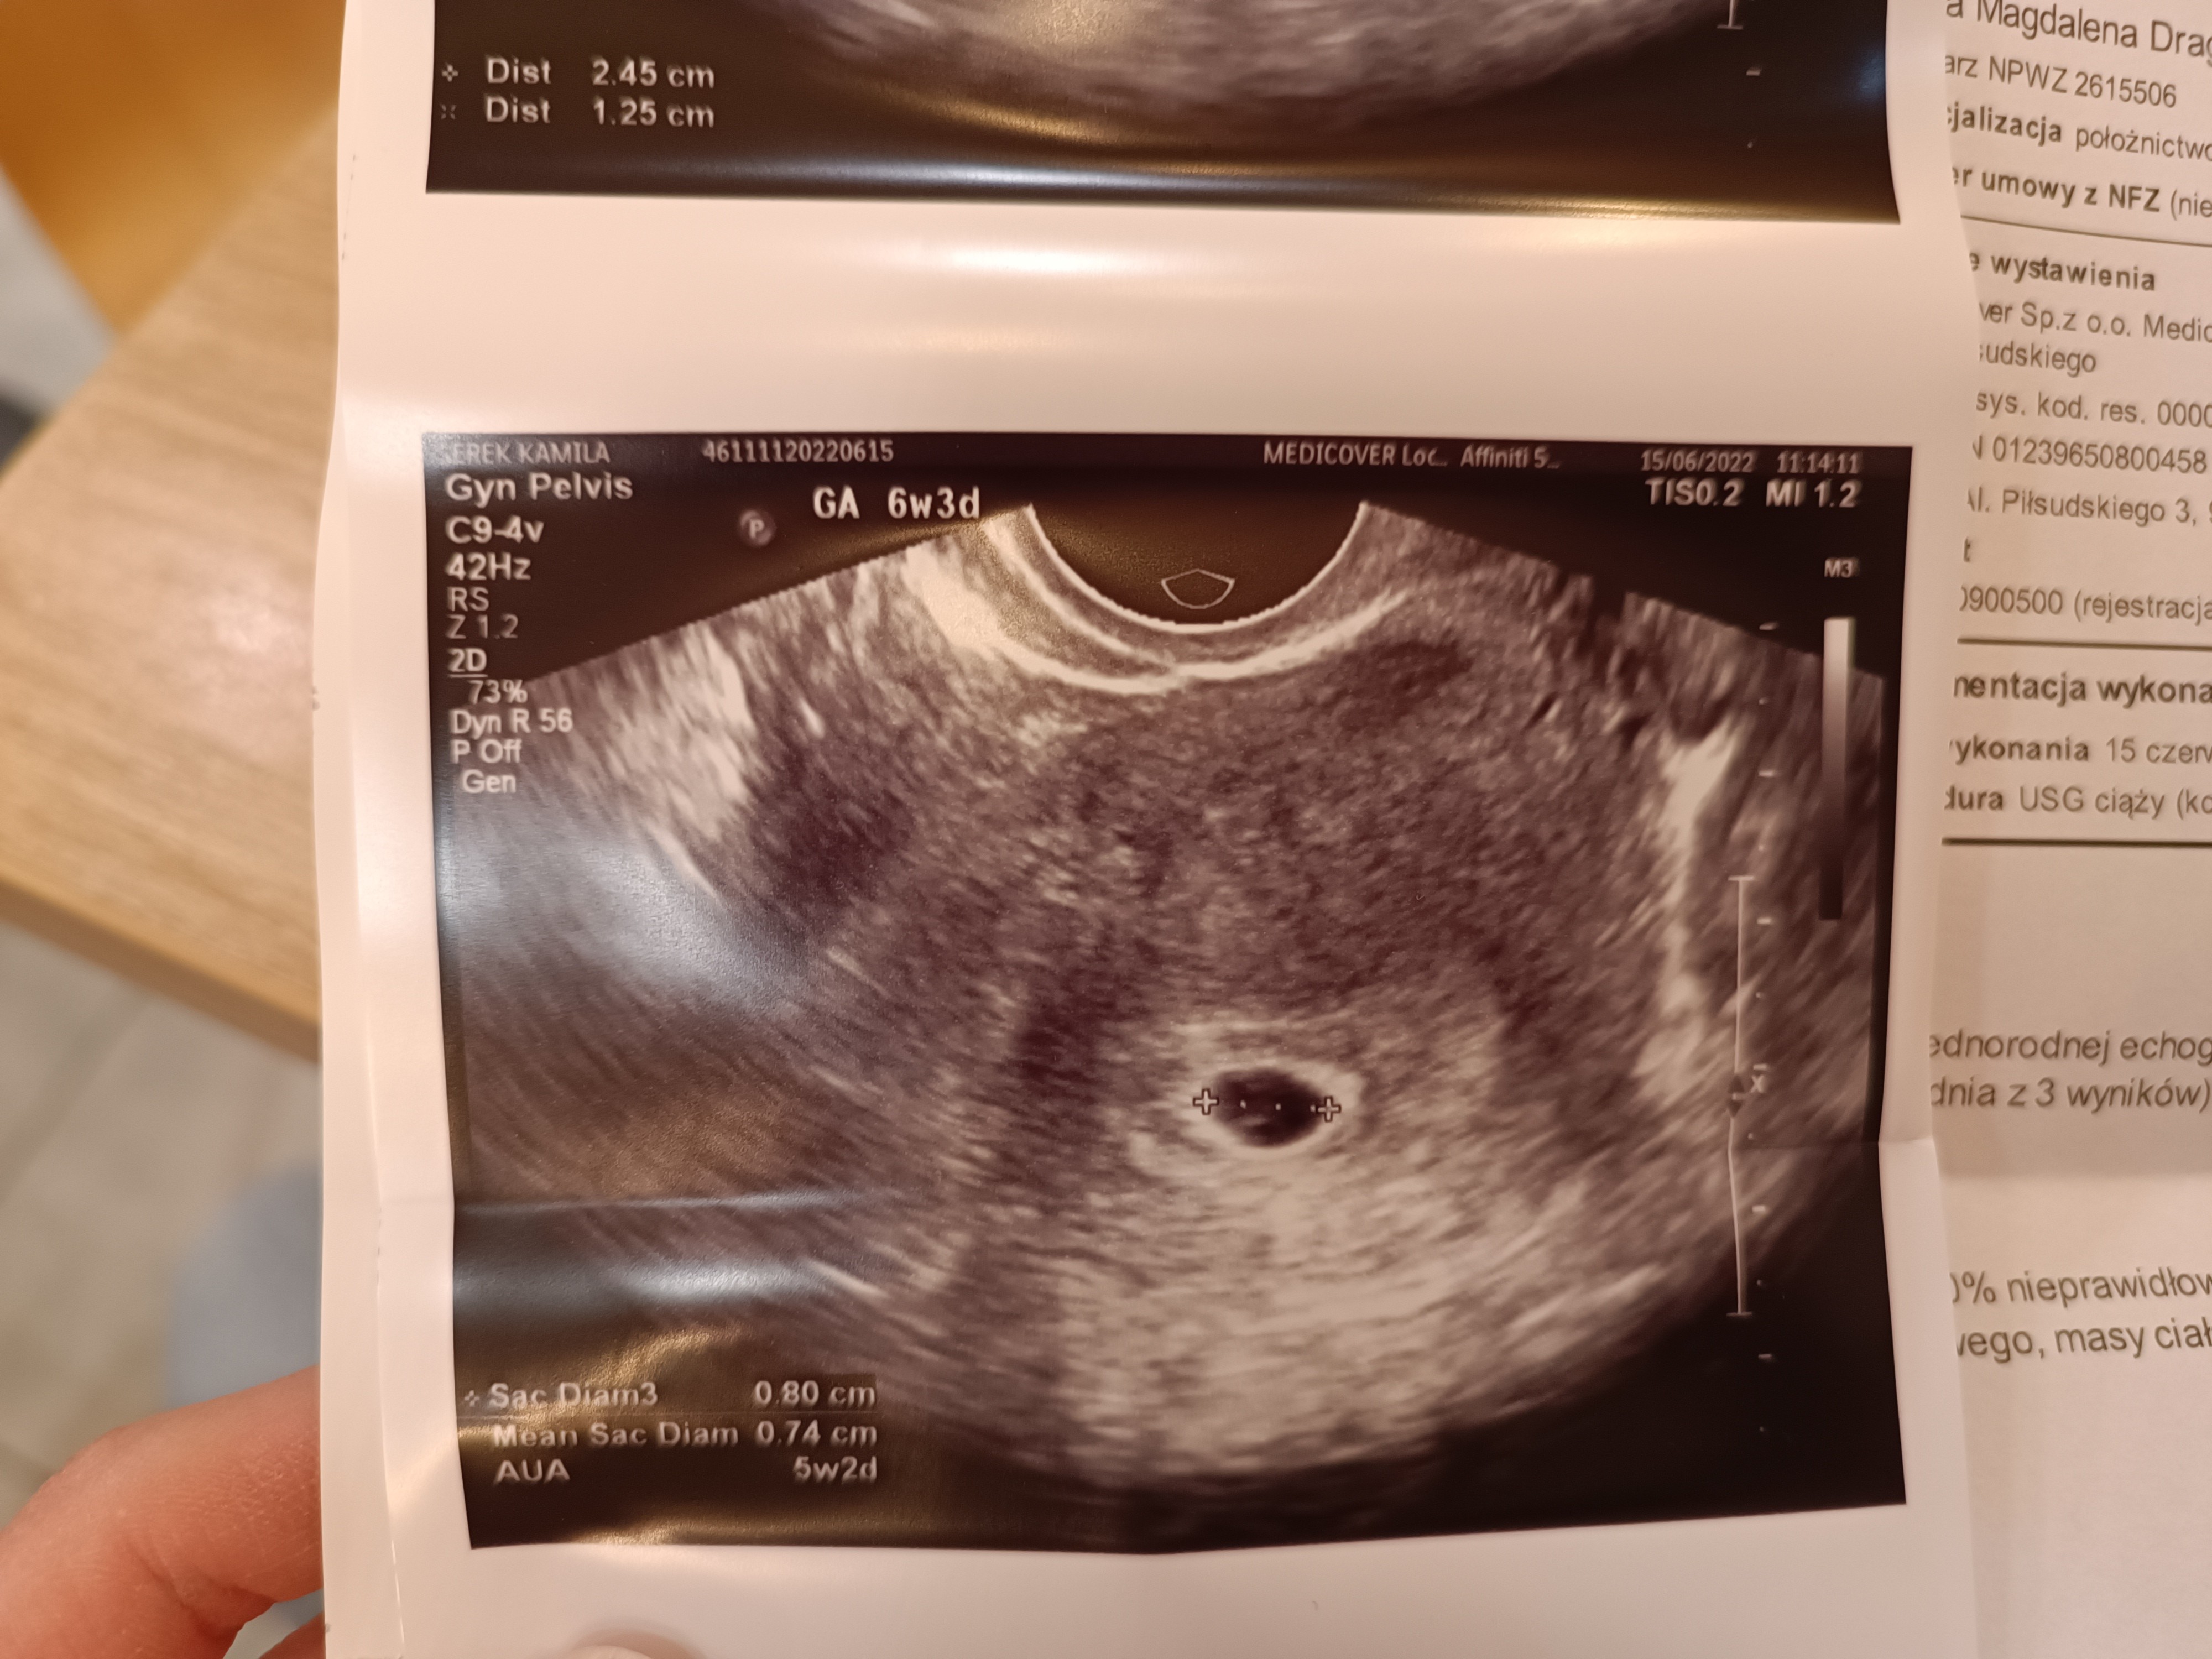

Z USG wyszło 5+2, bo mam późne owulacje i tak też mniej więcej się spodziewałam, mimo tego że z ostatniej miesiączki 6+3.

Jest pęcherzyk z pęcherzykiem zoltkowym. Kazała powtórzyć USG za 2,5 tygodnia i się nie denerwować. A ja już mam w samochodzie spakowana torbę do szpitala i byłam dziś na czczo, gotowa jechać na zabieg/laparoskopię. Jeszcze mnie policja za prędkość zatrzymała i bym się spóźniła na to USG choć wyszłam sporo wcześniej.

Załączniki

• IMG_20220615_114837.jpg

IMG_20220615_114837.jpg

1,4 MB · Wyświetleń: 111